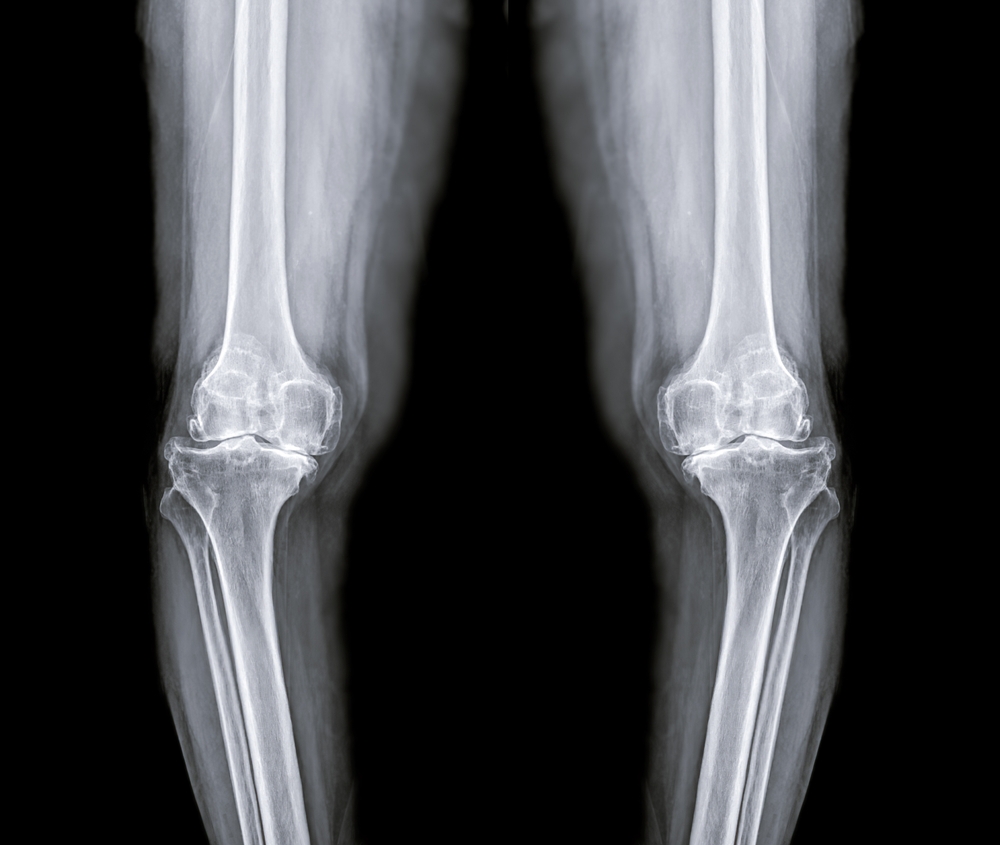

Three-month follow-ups showed complete healing without complications across patient population. X-rays confirmed solid bone union at fracture sites with no gaps, misalignments, or healing delays compared to traditional metal fixation methods.